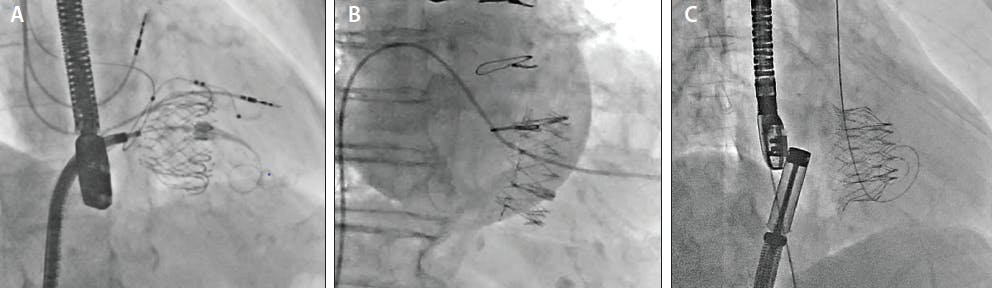

Figure 2. Tricuspid replacement devices. Fluoroscopic images of an Evoque valve (A), Gate system (B), and Intrepid TV (C). Figure 2B reprinted from JACC: Cardiovascular Interventions, 13/21, Rebecca T. Hahn, Susheel Kodali, Neil Fam, et al, Early multinational experience of transcatheter tricuspid valve replacement for treating severe tricuspid regurgitation, 2482-2493, Copyright (2020), with permission from Elsevier.